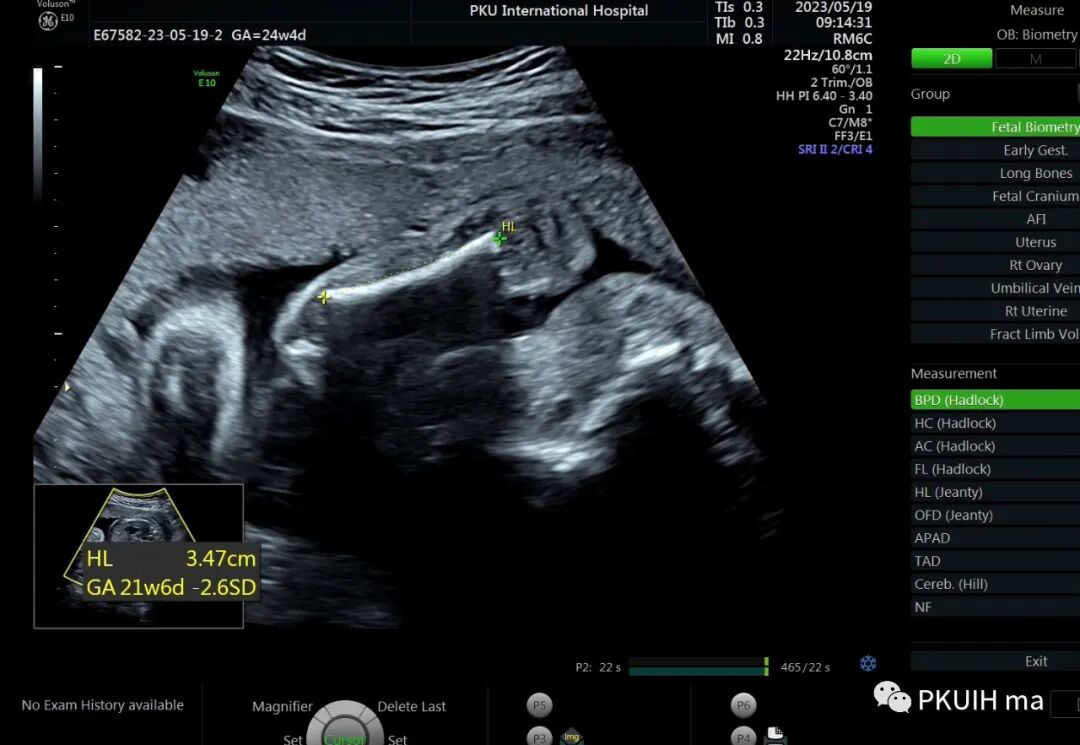

孕23周常规筛畸发现四肢长骨偏短,孕妇月经正常,核对早孕超声,孕周也没问题。

24周+复查发现还是肢体短,生长变慢

大多数孕期发现的骨骼发育不良通常表现为严重的短肢畸形,但足底长度通常不受累。正常时股骨长/足底长度约1:1,<0.87,考虑骨骼发育不良,同时在FGR的诊断中也有帮助。产前超声诊断的主要目的是识别出致死性的骨骼系统发育异常,对临床起到指导意义。区分致死和非致死性骨骼发育异常的主要超声指标有:1、严重的四肢短肢畸形,四肢所有长骨均低于该孕周平均值4个标准差,或股骨长度/胸围<0.16。2、严重的胸廓狭窄:胸围<胎龄的第5百分位,心胸比>0.6(一定要先除外心脏畸形),胸围/腹围比<0.89。3、某些特殊征象,比如严重的颅骨“三叶草样”畸形。